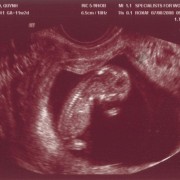

Ngày 11/28/1999 Ba Mẹ có nhau, lúc đó con ở đâu ha? Ngày 5/27/2008, con đây rồi!!! Mới được 2 tuần, là hạt nhân nhỏ xíu trong bụng Mẹ thôi Ngày 6/4/08, lần đầu tiên Ba Mẹ nghe tim con đập, 124 nhịp/phút. Mẹ sung sướng nhìn con. Còn Ba thì rơm rớm nước mắt, hihi!! Ngày 7/8/2008, con được 11 tuần rồi, bắt đầu có tay chân rồi đây... 1 tuần sau tay chân con đã dài ra rồi, lẹ ghê... ...biết nhào lộn vòng vòng nữa, mới nằm úp giờ nằm ngửa rồi. Ngày 9/3/2008, Mẹ chưa muốn biết con là trai hay gái vì muốn bất ngờ, nhưng rồi cuối cùng cũng không đợi được... ...hihi, cục cưng của Ba Mẹ là con trai. Con trai miệng bự giống Ba.  19 tuần là mắt mũi miệng đầy đủ hén. Từ khi biết có con, Mẹ nhờ Ba chụp hình hai mẹ con mình. Cái này là lúc con được 2 tháng trong bụng Mẹ.. ...24 tuần, con bắt đầu cựa quậy lung tung mỗi ngày... ...36 tuần, có lúc Ba Mẹ tưởng đã mất con nhưng con vẫn lớn giỏi ngoan... ..39 tuần, con nặng quá rồi nhưng Mẹ vẫn muốn con ở trong đó thêm chút nữa cho lớn lớn... Ba thì nôn gặp con quá, ngày nào Ba cũng nói chuyện với con.  Bụng Ba cũng bự rồi nè! Ngày 1/20/2009, con 39 tuần, bác sĩ muốn con ra sớm cho an toàn.  Ba Mẹ hồi hộp đợi tới lúc gặp con... Sau gần 8 tiếng chờ đợi thì con ra đời!! Con mở mắt nhìn Mẹ như là biết rồi đó.  Thương con ghê nơi! 1 tuần tuổi thì rụng rún.  2 tuần tuổi thì chụp hình lần đầu với Mẹ, nhỏ xíu xiu xiu... 7 tháng (8/2009) con bò lung tung, chụp hình mà không yên... 14 tháng (4/2010) con chỉ muốn chạy chơi thôi, Ba chụp lẹ lẹ nghe. Ngày 2/19/2010 Ba Mẹ làm lễ cưới ở nhà thờ.  Lần này thì có con rồi.  Có con Ba Mẹ có tất cả...